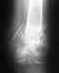

Здравствуйте.16.02.2013 упал с высоты 5 м. В результате закрытый перелом левой пяточной кости без смещения.

Наложили гипс и отправили домой.Когда можно будет вставать на ногу. и надо ли делать повторный снимок.

Эти вопросы уместно задать тому врачу, который видел рентгенограммы и принимал решения о выборе лечения. Переломы по форме разные, и нагрузка при каких-то безопасна раньше, при каких-то позже.